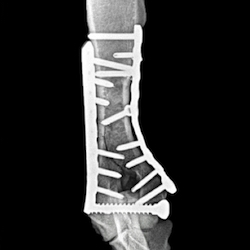

Cutting-edge surgical techniques supported by the latest evidence; TPLO for cruciate ligament tears. Management of patellar luxation, elbow, shoulder, hip & tarsal joint disease, MIPO techniques for complex fractures & limb deformities.